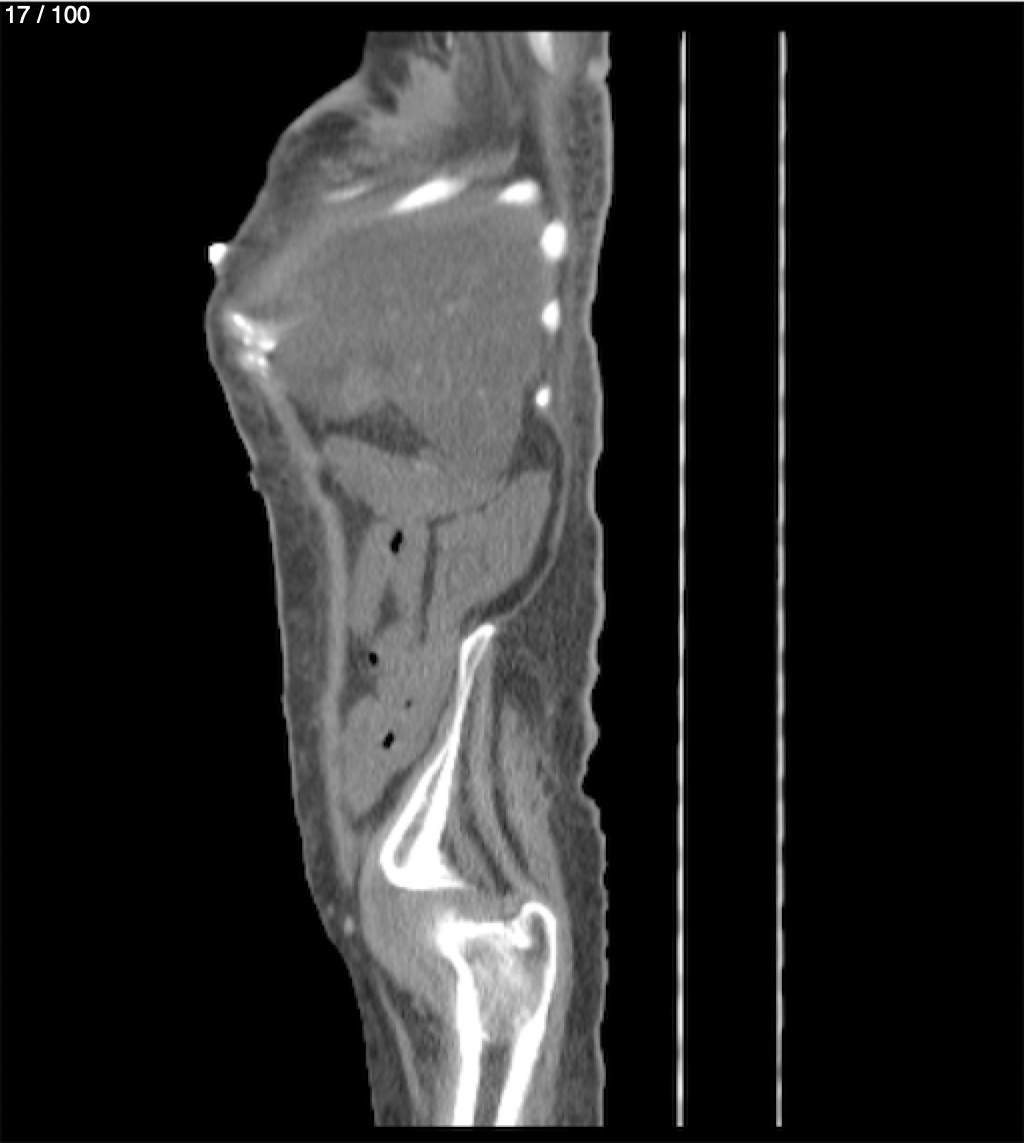

Hilda Geronimo Mendez 60A - T.C Abdomen Simple